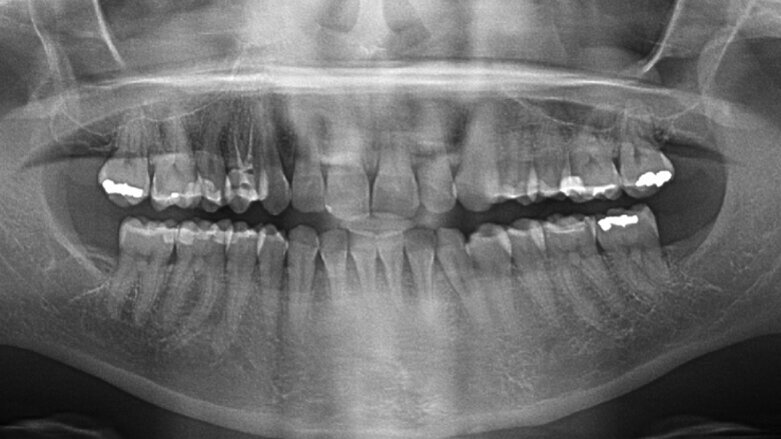

Con base en lo anterior se debe tener en cuenta que si un odontólogo es citado por un juez de cualquier nivel en la rama judicial de su país, debe acudir inmediatamente ante él para informarse de lo que le corresponde hacer. Varias de las posibles acciones que puede realizar o ejecutar son: peritazgo clínico en procesos ético disciplinarios o en demandas penales de pacientes contra odontólogos, conceptos especializados sobre la ejecución, pertinencia y conveniencia de tratamientos o intervenciones realizadas por odontólogos en pacientes que no tuvieron los resultados esperados, o en la identificación o reconocimiento de los cadáveres de los cuales no se sabe quiénes son, o de los cadáveres denominados N.N, Nomen Nescio, que significa desconozco el nombre; este término se utiliza para las personas que se han encontrado muertas en fosas comunes, o en alguna otra parte del territorio, y aun habiéndoles practicado exámenes de recolección de ADN, muestras de sangre, saliva, orina, semen, odontológicos, no se identifica quiénes son.